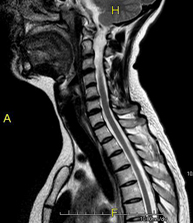

- RM de columna cervical

Prova diagnòstica no invasiva que consisteix en l'obtenció d'imatges d'alta definició anatòmica de la columna cervical mitjançant l'ús d'un camp electromagnètic i ones de ràdio (com un emissor i un receptor). No utilitza radiació ionitzant. Indicacions: traumatisme, degeneració de la columna, hèrnies. - RM de columna dorsal

- RM Columna Cervical

Prueba diagnóstica no invasiva que consiste en la obtención de imágenes de alta definición anatómica de la columna cervical mediante el empleo de un campo electromagnético y ondas de radio (con un emisor y un receptor). No utiliza radiación ionizante. Indicaciones: traumatismo, degeneración de la columna, hernias. - RM Columna Dorsal